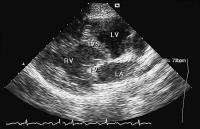

Abbildung 2: Vierkammerblick: Die linksseitig gelegene AV-Klappe (morphologisch Trikuspidalklappe, TV) inseriert weiter apikal als die rechtsseitige AV-Klappe (morphologisch Mitralklappe, MV): die typische Dreiecksform des linken Herzohrs charakterisiert den linken Vorhof (LA); LV = (morphologisch) linker Ventrikel, RA = rechter Vorhof, RV = (morphologisch) rechter Ventrikel.